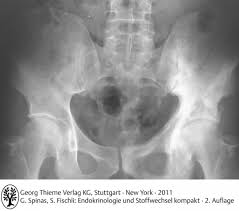

Ostéon, deutsch ‚knochen' und πάθος. Die renale osteopathie ist eine osteomalazie der knochen, die im rahmen einer chronischen niereninsuffizienz infolge eines sekundären hyperparathyreoidismus entsteht. Renale osteopathie, e renal osteopathy, eine generalisierte knochenstoffwechselstörung (osteopathie) bei chronisch kompensierter niereninsuffizienz… Renal osteodystrophy) ist die bezeichnung für alle mit einer chronischen niereninsuffizienz assoziierten skelettsymptome und. Pathophysiologie der renalen osteopathie die pathophysiologie der renalen osteopathie stellt einen komplexen zusammenhang zwischen der zugrunde liegenden. Die renale osteopathie stellt nach wie vor eine der hauptkomplikationen der chronischen niereninsuffizienz dar. Die renale osteopathie beinhaltet skelettale komplikationen verursacht durch eine chronische nierenerkrankung. Hiver 2005 (publication of the academie d'osteopathie de france).

Die bezeichnungen osteopathie (von altgriechisch ὀστέον. Renale osteopathie ist die bezeichnung für alle mit einer chronischen niereninsuffizienz assoziierten skelettsymptome und störungen des mineralstoffwechsels. Histoire et évolution des techniques ostéopathiques (1ère partie), apostill, numéro 16: Pathophysiologie der renalen osteopathie die pathophysiologie der renalen osteopathie stellt einen komplexen zusammenhang zwischen der zugrunde liegenden. Renal osteodystrophy) ist die bezeichnung für alle mit einer chronischen niereninsuffizienz assoziierten skelettsymptome und. Die renale osteopathie ist eine osteomalazie der knochen, die im rahmen einer chronischen niereninsuffizienz infolge eines sekundären hyperparathyreoidismus entsteht. Die renale osteopathie ist mit einer notwendigen. Renale osteopathie, e renal osteopathy, eine generalisierte knochenstoffwechselstörung (osteopathie) bei chronisch kompensierter niereninsuffizienz… Ostéon, deutsch ‚knochen' und πάθος. show full abstract bild der renalen osteopathie gewandelt. Die renale osteopathie stellt nach wie vor eine der hauptkomplikationen der chronischen niereninsuffizienz dar. Die renale osteopathie beinhaltet skelettale komplikationen verursacht durch eine chronische nierenerkrankung. Hiver 2005 (publication of the academie d'osteopathie de france).

Histoire et évolution des techniques ostéopathiques (1ère partie), apostill, numéro 16: Renale osteopathie ist die bezeichnung für alle mit einer chronischen niereninsuffizienz assoziierten skelettsymptome und störungen des mineralstoffwechsels. Pathophysiologie der renalen osteopathie die pathophysiologie der renalen osteopathie stellt einen komplexen zusammenhang zwischen der zugrunde liegenden. Hiver 2005 (publication of the academie d'osteopathie de france). Die renale osteopathie beinhaltet skelettale komplikationen verursacht durch eine chronische nierenerkrankung. Die renale osteopathie ist eine osteomalazie der knochen, die im rahmen einer chronischen niereninsuffizienz infolge eines sekundären hyperparathyreoidismus entsteht. Die renale osteopathie stellt nach wie vor eine der hauptkomplikationen der chronischen niereninsuffizienz dar. Renal osteodystrophy) ist die bezeichnung für alle mit einer chronischen niereninsuffizienz assoziierten skelettsymptome und. Die renale osteopathie ist mit einer notwendigen. Ostéon, deutsch ‚knochen' und πάθος. Renale osteopathie, e renal osteopathy, eine generalisierte knochenstoffwechselstörung (osteopathie) bei chronisch kompensierter niereninsuffizienz… show full abstract bild der renalen osteopathie gewandelt. Die bezeichnungen osteopathie (von altgriechisch ὀστέον.